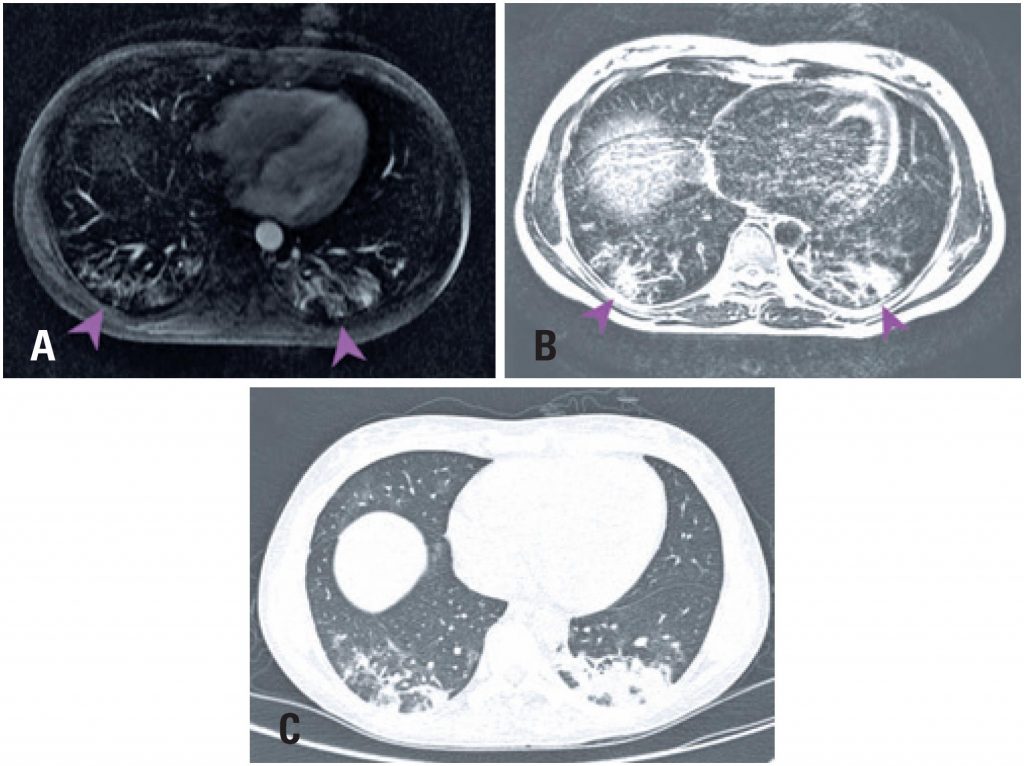

A 34-year-old woman with a personal history of ulcerative rectocolitis for 5 years who were using sulphasalazine and mesalazine. The patient was admitted to the emergency unit presenting asthenia, dyspnea, fever, cough with hemoptoic sputum for 8 days, and oxygen saturating by 97% in room air. The computed tomography (CT) () showed sparse ground-glass opacities, although more evident in the posterior contour of lower lobes. She was hospitalized and tested positive for coronavirus infection identified through real-time reverse-transcription-polymerase-chain-reaction (RT-PCR) test. During the hospitalization she presented diffuse abdominal pain with liquid, dark, and foul-smelling stools, and underwent an upper abdominal magnetic resonance.

Magnetic resonance imaging cuts () showed bilateral ground-glass opacities in lung bases with posterior and subpleural predominance with similar aspects to those showed in the CT.